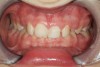

Figure 7  Patients who combine tongue pressure to clear the airway and GERD can produce wear on the lingual surfaces resembling bulimia. It is not restricted to maxillary anteriors.

Figure 7

Some of the acid content of the stomach may reach the oral cavity. This is an extremely destructive acid with a pH of 1 to 2. In comparison, dietary acids are greater than pH 3. The most common site for damage is the palatal surface of the maxillary molars (Figure 5 and Figure 6). Reflux symptoms present mostly in a supine position. The dorsum of the tongue pushes the acid to the maxillary molar palatal surface when swallowing to buffer the acid.42 While the palatal surface is the most common site of destruction, the pattern of damage will be dictated by the sleep position of the patient during the episodes. Tongue activity associated with airway patency coupled with regurgitation may also create wear on the lingual surfaces of teeth resembling bulimia but are not limited to the maxillary anteriors (Figure 7). GERD patients have a significantly higher risk of xerostomia and oral burning sensation.43 This lack of lubrication paired with acid-roughened surfaces increase the risk of frictional wear associated with sleep bruxism.